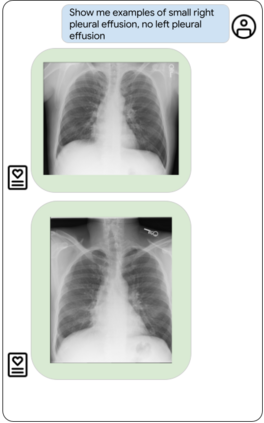

Our approach, which we call Embeddings for Language/Image-aligned X-Rays, or ELIXR, leverages a language-aligned image encoder combined or grafted onto a fixed LLM, PaLM 2, to perform a broad range of tasks. We train this lightweight adapter architecture using images paired with corresponding free-text radiology reports from the MIMIC-CXR dataset. ELIXR achieved state-of-the-art performance on zero-shot chest X-ray (CXR) classification (mean AUC of 0.850 across 13 findings), data-efficient CXR classification (mean AUCs of 0.893 and 0.898 across five findings (atelectasis, cardiomegaly, consolidation, pleural effusion, and pulmonary edema) for 1% (~2,200 images) and 10% (~22,000 images) training data), and semantic search (0.76 normalized discounted cumulative gain (NDCG) across nineteen queries, including perfect retrieval on twelve of them). Compared to existing data-efficient methods including supervised contrastive learning (SupCon), ELIXR required two orders of magnitude less data to reach similar performance. ELIXR also showed promise on CXR vision-language tasks, demonstrating overall accuracies of 58.7% and 62.5% on visual question answering and report quality assurance tasks, respectively. These results suggest that ELIXR is a robust and versatile approach to CXR AI.